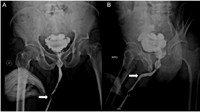

Seorang pria di Kalimantan Timur mengeluhkan sakit di alat kelaminnya. Ternyata, pria 48 tahun itu memasukkan sejumlah benda asing seperti kabel listrik, alat ekstraktor kartu SIM, hingga karet gelang. (Foto: Radiology Cases Reports)